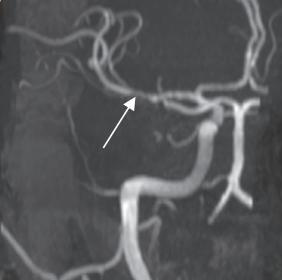

MR angiography: “Skipped” or “segmental” pattern of

vessel involvement seen — a classical radiological hallmark

of PACNS. This refers to alternating areas of stenosis and

normal-caliber segments across multiple intracranial vessels,

reflecting multi focal vasculitic inflammation.

The turning point in diagnosis was the detailed review of

sequential MRI findings, which revealed microhemorrhages in the

cerebellum and brainstem, along with perivascular enhancement and

MR angiography revealing skipped and segmental pattern of vessel

involvement — features more characteristic of PACNS than TB. The